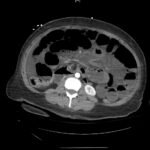

Recognition of the whirl sign on computed tomography (CT) imaging can improve patient outcomes in those presenting with small bowel obstruction (SBO). In the case highlighted in this report, a 40-year-old woman with a remote history of gastric bypass presented to the emergency department (ED) with four hours of abdominal pain and vomiting. Findings on the initial CT of the abdomen and pelvis were suggestive of SBO with a whirl sign pattern. The whirl sign occurs after the bowel rotates around the mesentery, leading to a visual “whirl” of mesenteric vessels. Unfortunately, despite prompt diagnosis, the patient developed an ischemic bowel and ultimately sustained a prolonged hospital course requiring multiple bowel resections. ED providers should familiarize themselves with the whirl sign because its presence in patients with SBO increases the likelihood of ischemia. These patients should have urgent surgical consultation to decrease overall morbidity and mortality.